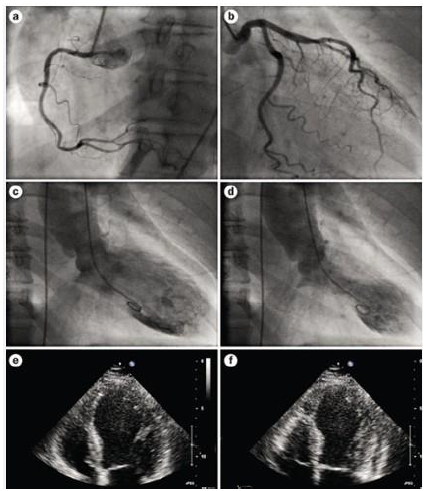

Analise as afirmativas quanto aos exames ECG, cineangiocoronariografia, ecocardiograma e quadro clínico abaixo descritos.

Paciente, 72 anos, hipertensa, não diabética, não tabagista, foi trazida pelo SAMU à sala de emergência com quadro de precordialgia típica súbita, palpitações e sudorese difusa, após receber um telefonema com um suposto sequestro de seu filho. Após a avaliação inicial, foram realizados ECG, ECO, troponina (resultado três vezes o valor de referência) e cineangiocoronariografia.

Fonte: : https://hqmeded-ecg.blogspot.com/2010/12 consulta em 25/02/2024

Fonte: https://www.nature.com/articles/nrcardio.2010.16 consulta em 25/02/2024.

I. TINOCA com cardiomiopatia catecolaminérgica.

II. TINOCA com miocardite viral.

III. MINOCA.

IV. IAM do tipo I.

V. Síndrome de Takotsubo.

Sobre os diagnósticos apresentados acima, estão corretas apenas as afirmativas